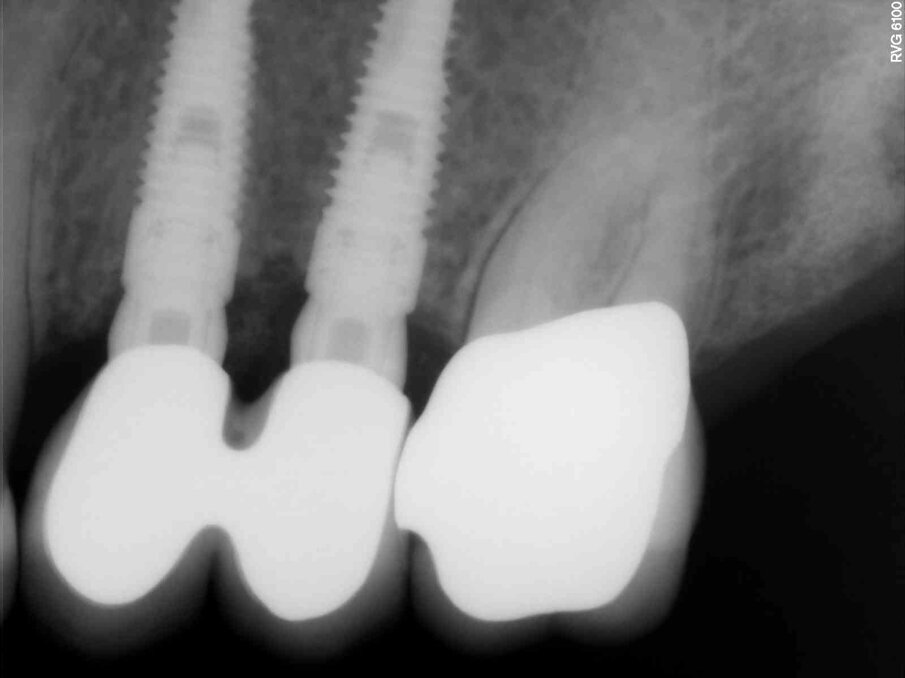

Fig. 1d_Tessuti duri prima e dopo la tecnica S.A.T., posizionamento implantare.

Fig. 7_Primo caso eseguito nel 2011, rx di controllo a 3 anni dal posizionamento implantare.